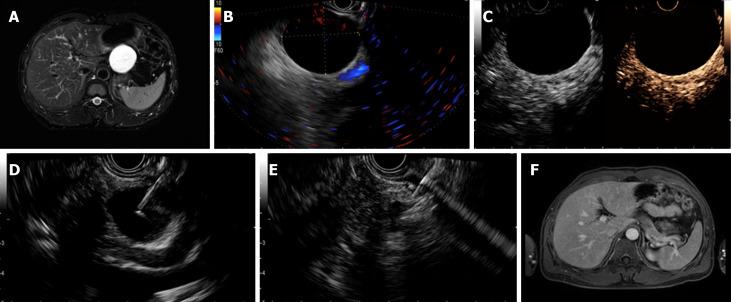

Endoscopic ultrasound-guided injective ablative treatment of pancreatic cystic neoplasms.

With the development of cross-sectional imaging modalities and the increasing attention being paid to physical examinations, the prevalence of pancreatic cystic neoplasms (PCNs) has increased. PCNs comprise a broad differential spectrum with some PCNs having low or no malignant potential and others having high malignant potential. The morbidity and mortality rates related to major pancreatic surgical resection are high. Long-term surveillance may not only increase the financial burden and psychological stress for patients but also result in a missed malignancy. Minimally invasive endoscopic ultrasound (EUS)-guided ethanol ablation was first reported in 2005. Several other agents, such as paclitaxel, lauromacrogol, and gemcitabine, were reported to be effective and safe for the treatment of PCNs. These ablative agents are injected through a needle inserted into the cyst transgastric or transduodenal puncture. This treatment method has been substantially developed in the last 15 years and is regarded as a promising treatment to replace surgical resection for PCNs. While several reviews of EUS-guided ablation have been published, no systematic review has evaluated this method from patient preparation to follow-up in detail. In the present review, we systematically describe EUS-guided injective ablation with regard to the indications, contraindications, preoperative treatment, endoscopic procedure, postoperative care and follow-up, evaluation method, treatment efficiency, safety profile, tips and tricks, and current controversies and perspectives.